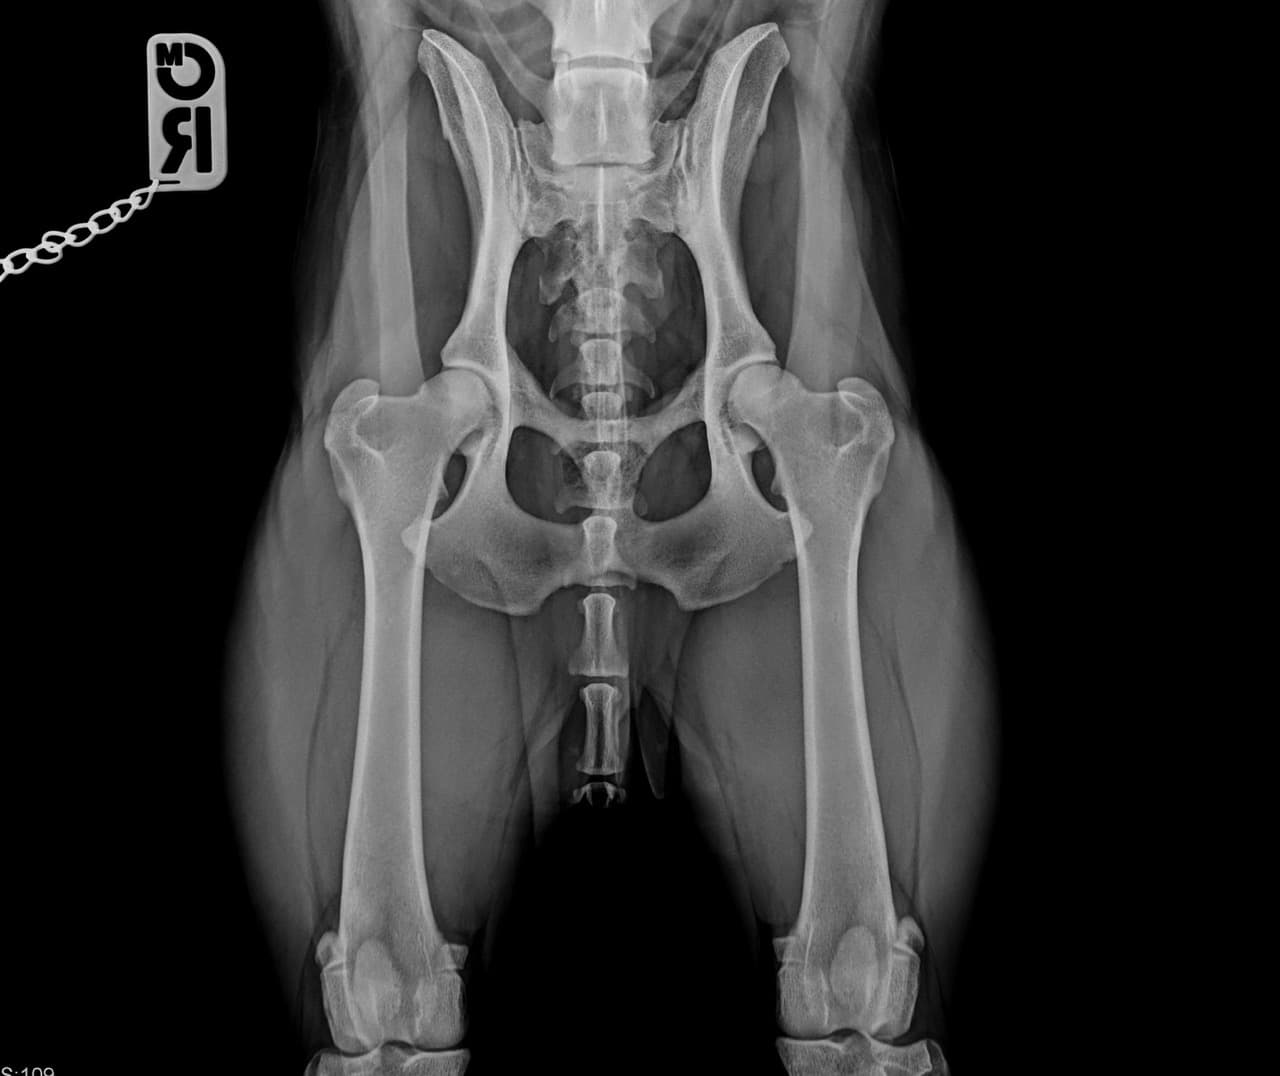

- Zuchtuntersuchung (HD und ED-Röntgen, Patella-Lux)

- Digitales Röntgen (DR-System)

- Gelenkchirurgie (Kreuzbandriss: TTA Tight Rope, lateraler Fadenzügel) (Patella Lux: Ridge Stop, Transposition Tuberositas tibiae auch kombiniert mit TTA) Hüftgelenksluxation